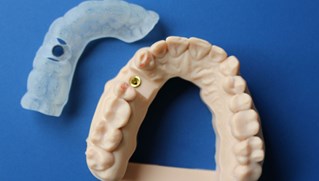

Inför operationen framställs en guideskena som underlättar operationen och ger oss en stor precision vid placeringen av titanskruven (fixturen)